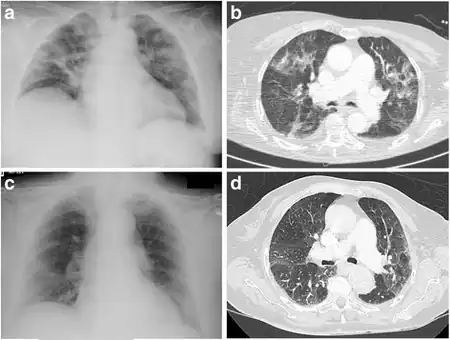

a,c)X-ray , b,d) computed tomography for individual(s) with eosinophilic pneumonia

Eosinophilic pneumonia is diagnosed in one of three circumstances: when a complete blood count reveals increased eosinophils and a chest X-ray or computed tomography identifies abnormalities in the lungs, when a biopsy identifies increased eosinophils in lung tissue, or when increased eosinophils are found in fluid obtained by a bronchoscopy (bronchoalveolar lavage fluid). Association with medication or cancer is usually apparent after review of a person's medical history. Specific parasitic infections are diagnosed after examining a person's exposure to common parasites and performing laboratory tests to look for likely causes. If no underlying cause is found, a diagnosis of acute or chronic eosinophilic pneumonia is made based upon the following criteria. Acute eosinophilic pneumonia is most likely with respiratory failure after an acute febrile illness of usually less than one week, changes in multiple areas and fluid in the area surrounding the lungs on a chest X-ray, and eosinophils comprising more than 25% of white blood cells in fluid obtained by bronchoalveolar lavage. Other typical laboratory abnormalities include an elevated white blood cell count, erythrocyte sedimentation rate, and immunoglobulin G level. Pulmonary function testing usually reveals a restrictive process with reduced diffusion capacity for carbon monoxide. Chronic eosinophilic pneumonia is most likely when the symptoms have been present for more than a month. Laboratory tests typical of chronic eosinophilic pneumonia include increased levels of eosinophils in the blood, a high erythrocyte sedimentation rate, iron deficiency anemia, and increased platelets. A chest X-ray can show abnormalities anywhere, but the most specific finding is increased shadow in the periphery of the lungs, away from the heart.